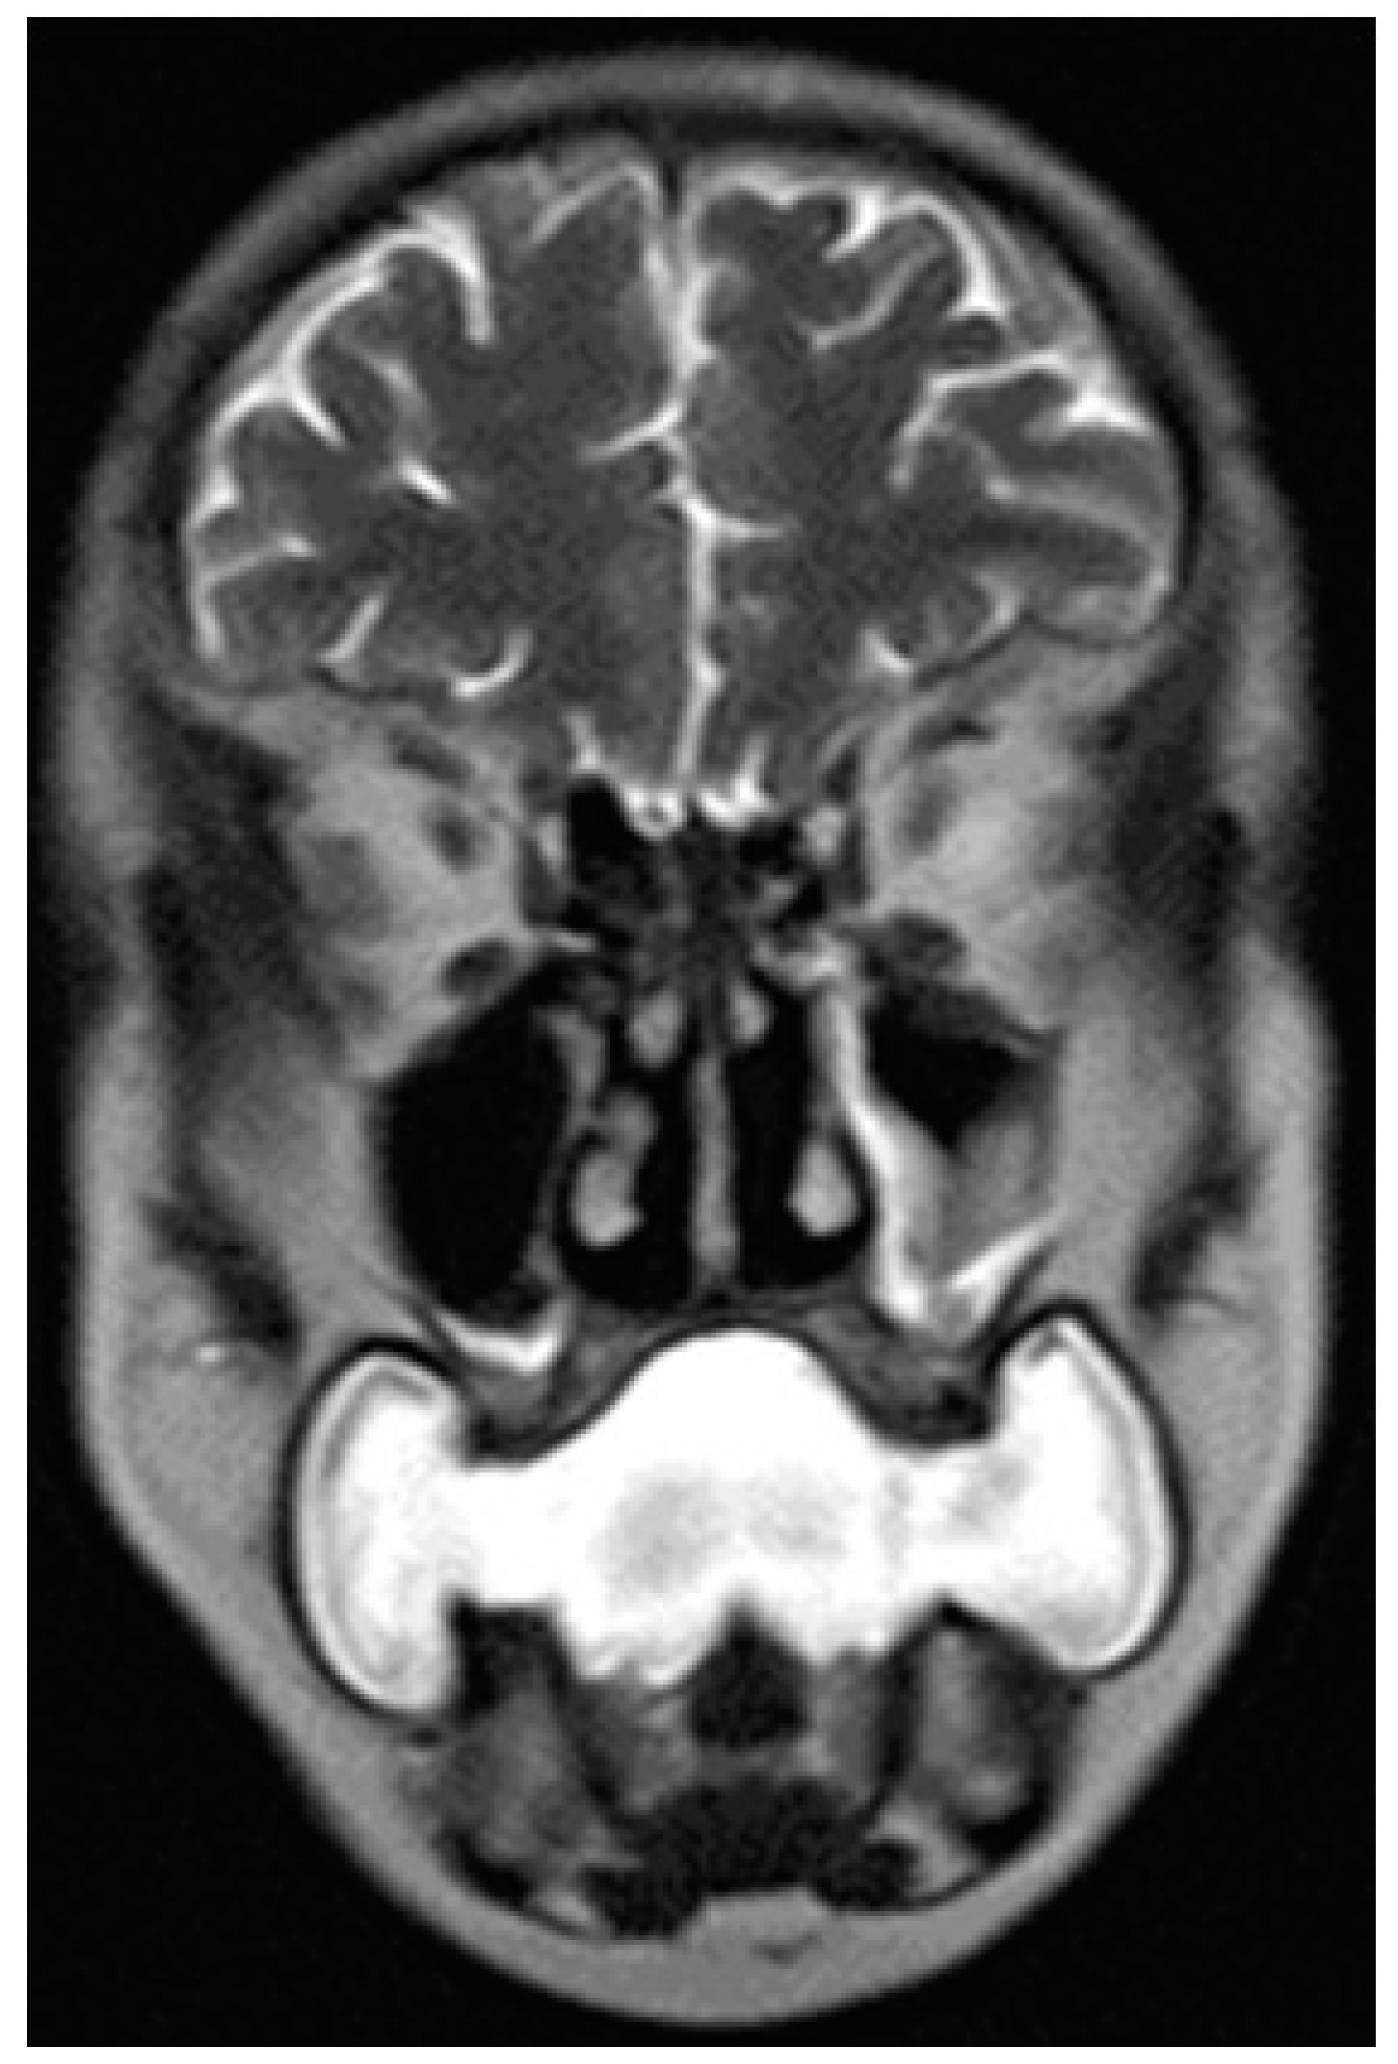

- Water distension of the oral vestibule. This technique is exclusively used on MRI examinations since MRI has a high contrast for liquids by using specific sequences, especially T2 sequences. Water distension of the oral vestibule is performed by asking patients to drink 20–40 mL of still water and keep it in the mouth for the time necessary to acquire the images (T2 and pre- and post-contrast T1 sequences) [47]. This manoeuvre distends the oral vestibule and the presence of water provides excellent natural contrast between the lesion and the adjacent mucosal surfaces (Figure 17).